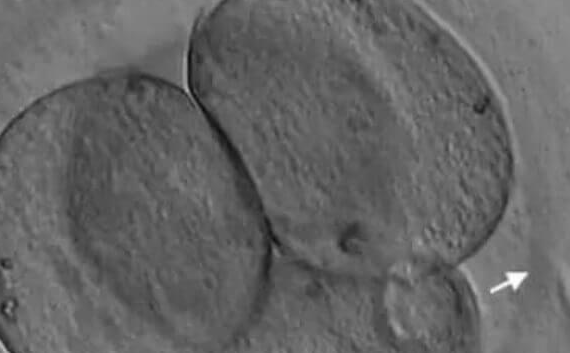

女性年龄超过35岁后,卵巢功能显著衰退,卵子质量下降直接导致胚胎透明带异常。透明带作为胚胎的“保护壳”,在自然孵化过程中需被胚胎分泌的酶溶解。然而,高龄女性的透明带常出现两大问题:

厚度增加:临床数据显示,35岁以上女性胚胎透明带厚度普遍超过15微米,部分甚至达22微米,远超自然孵化的临界值(10-12微米)。

弹性丧失:透明带糖蛋白结构因氧化应激和代谢异常变得僵硬,酶解效率降低,导致胚胎无法在种植窗开放时同步孵出。

冷冻胚胎特殊处理:解冻后透明带硬化加剧,需在移植前进行二次薄化。